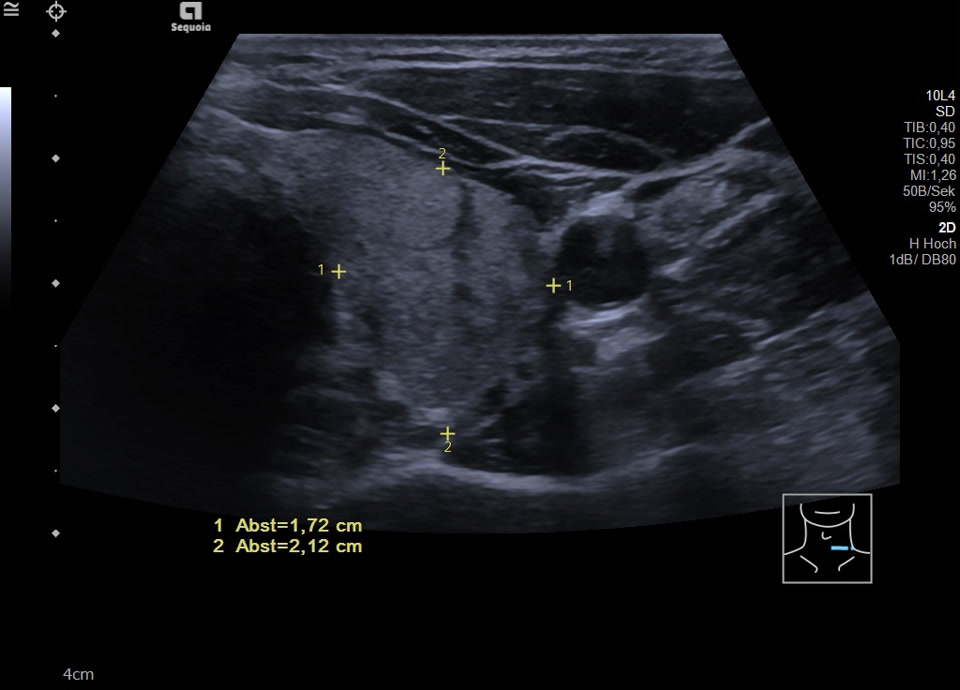

45-year-old male presented patient with persistent sore throat and general symptoms following an EBV-infection. An external diagnosis of post-infectious de Quervain’s thyroiditis had already been made, and a two-week course of corticosteroid therapy was administered. Initial clinical improvement with reduced throat pain was noted under treatment, but symptoms reoccurred after discontinuation of corticosteroids. Laboratory findings revealed leukocytosis of 12,000/µl and CRP of 113 mg/l. Sonographically, a bilaterally enlarged thyroid gland with diffusely hypoechoic areas and inhomogeneous parenchyma was observed. Combined with the patient history, this was characteristic of a subacute thyroiditis with relapse after short-term corticosteroid therapy. Prolonged corticosteroid therapy with slow tapering was performed. Under this regimen, marked clinical improvement occurred within weeks; follow-up ultrasound four months later showed a normal-sized thyroid with only mildly inhomogeneous parenchyma, consistent with resolving thyroiditis.